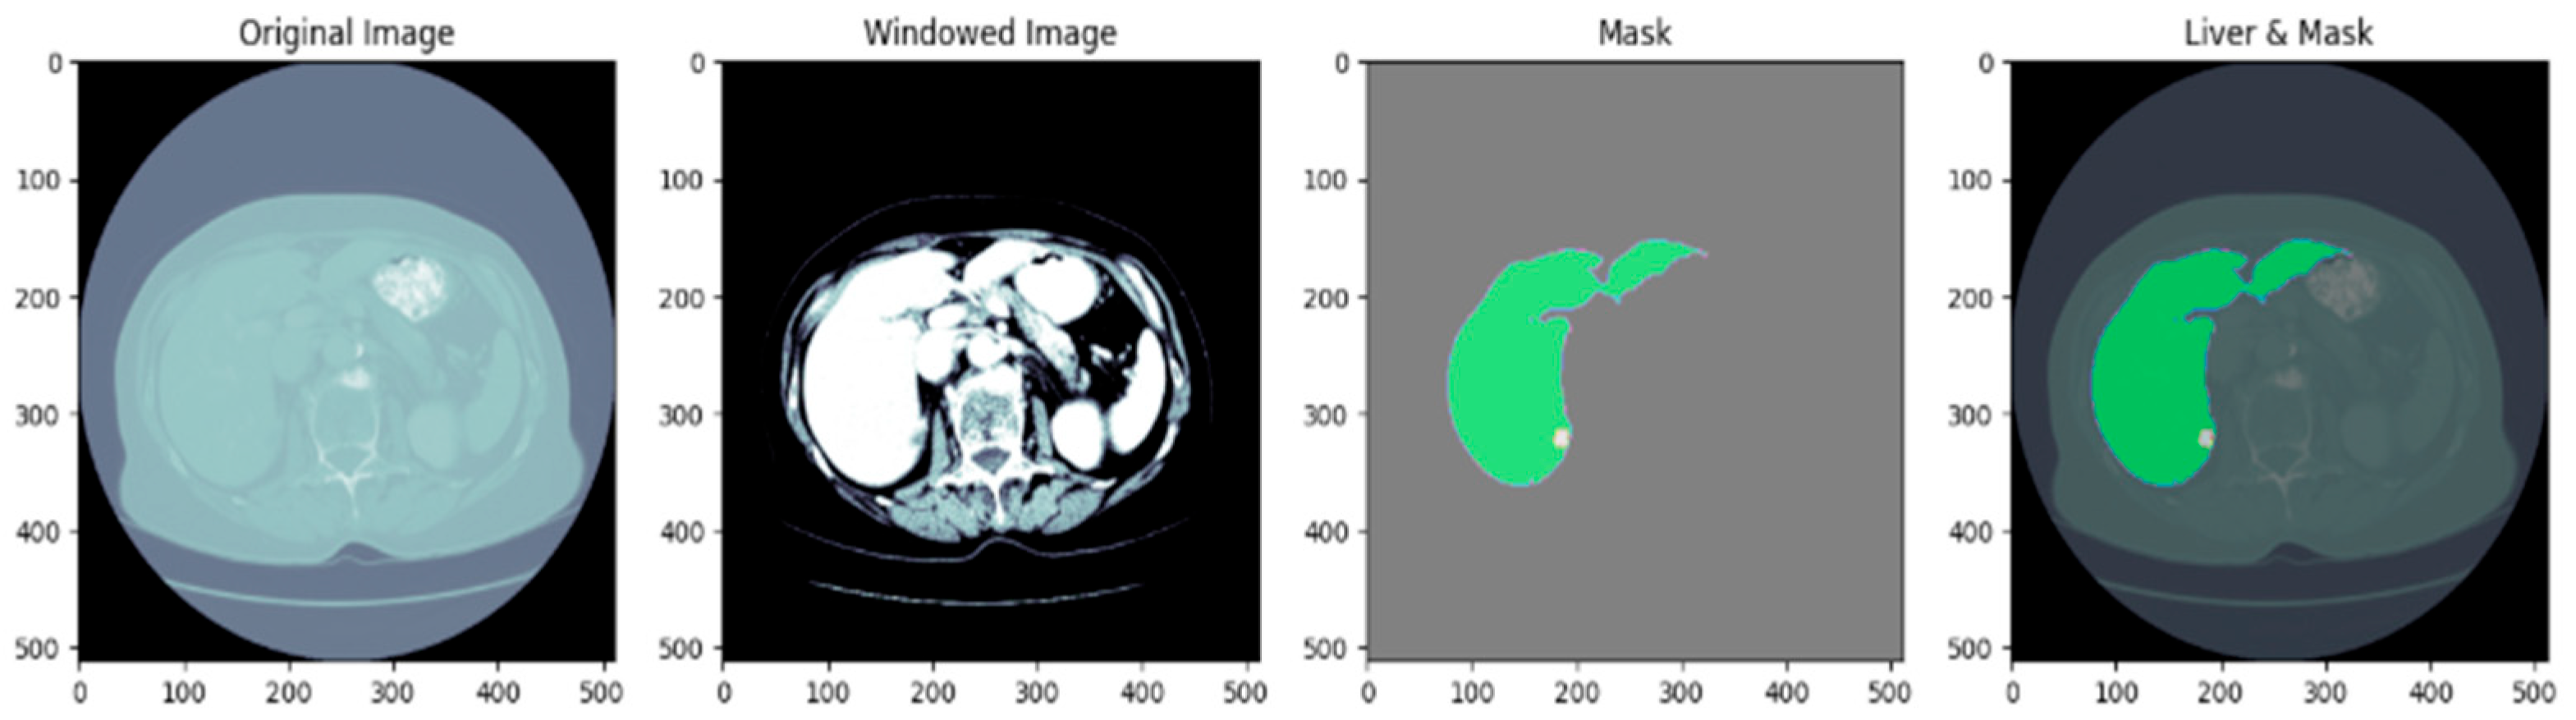

3.2. Dataset Preprocessing

3.3. Based Model Architecture

3.5. Proposed U-Net Segmentation with WOA